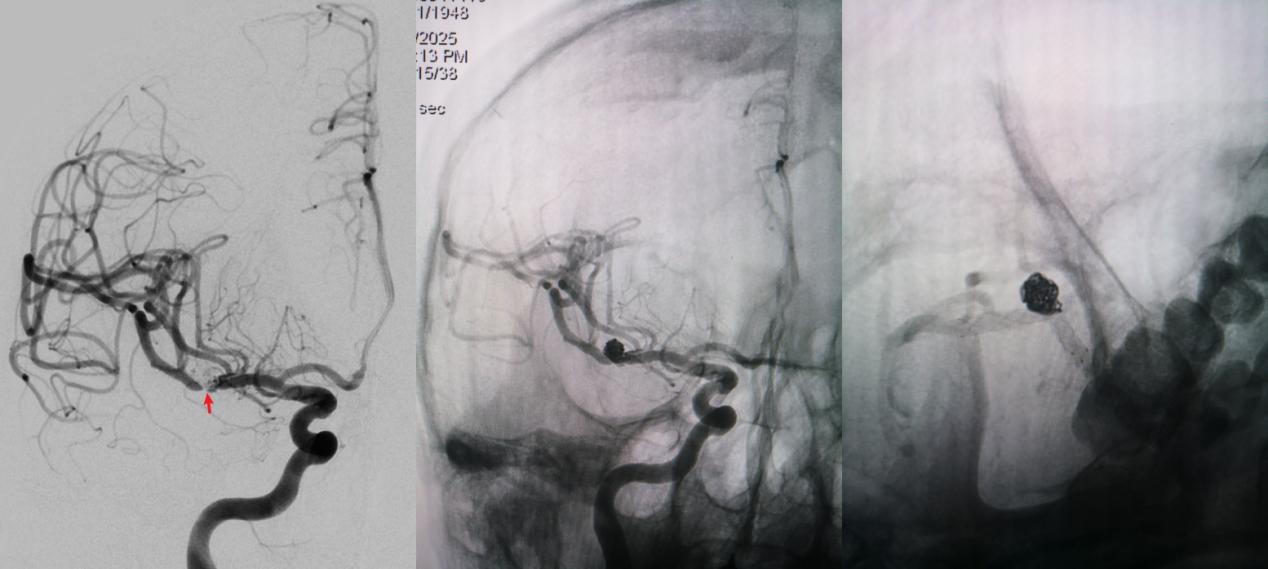

病例一为77岁女性患者,既往高血压病史。因“突发剧烈头痛伴恶心2天”前来清华大学附属垂杨柳医院急诊科就诊。头颅CT检查提示蛛网膜下腔出血,头颈动脉CTA提示右侧大脑中动脉M1段分叉处宽颈动脉瘤。神经外科脑血管病介入团队急诊为患者实施了全脑血管造影术(DSA),造影显示动脉瘤不规则,可见子囊,宽颈,主要累及下干。团队采取了支架辅助弹簧圈栓塞术,患者颅内“不定时炸弹”被成功拆除。动脉瘤达到致密栓塞,载瘤动脉通畅。住院半个月后顺利出院,无神经功能障碍。

▲术前DSA显示宽颈动脉瘤,有子囊,主要累及下干

▲术后DSA显示动脉瘤致密栓塞,载瘤动脉通畅

病例二为58岁女性患者。因“突发剧烈头痛伴呕吐3小时”就诊于清华大学附属垂杨柳医院急诊科,行头颅CT检查提示蛛网膜下腔出血。患者嗜睡,频繁呕吐,不排除颅内再出血。为争分夺秒抢救患者生命,神经外科脑血管病介入团队紧急为患者实施了DSA,显示左侧大脑中动脉分叉处宽颈动脉瘤,主要累及下干。术中采取双微导管技术,于动脉瘤内填塞弹簧圈,并置入一枚支架保证致密栓塞和下干分支血管的通畅。成功“拆弹”,化险为夷,患者恢复过程顺利,出院时无神经功能缺损。

▲术前DSA显示左侧大脑中动脉分叉宽颈动脉瘤,可见子瘤,主要累及下干